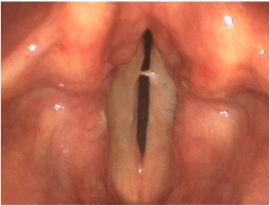

How are vocal cord cancers diagnosed?

The vocal cords are unable to be seen by looking in the back of your throat. Suspicious lesions can be identified on videostroboscopy in our office. Definitive diagnosis of a vocal cord cancer requires a biopsy with analysis of the tissue underneath a microscope by a pathologist. If you choose to pursue laser surgery, a biopsy and removal of the cancer can be performed at the same time to prevent the need for multiple surgeries.